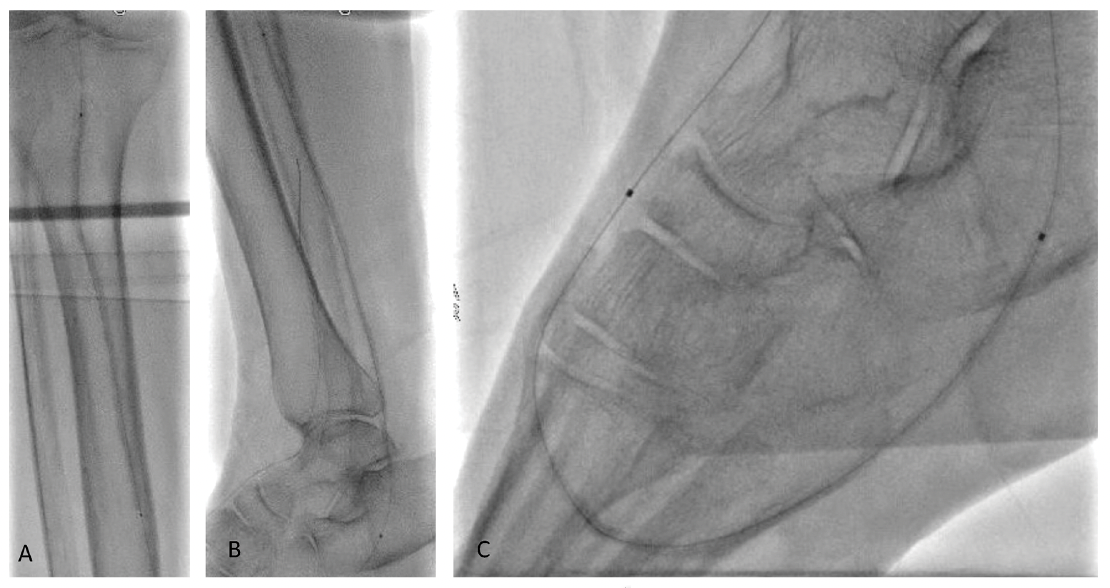

Another major difference is that we have not seen any concerns with distal embolization and slow-flow phenomenon with the use of the MagicTouch sirolimus-coated balloon (SCB), even in very distal and small BTK arteries (Figures 1-4). Conversely, with paclitaxel-coated balloons, 8% rates of slow-flow phenomenon due to distal embolization have been described.1 This raises concerns of thrombotic risks with the use of paclitaxel-coated balloons in distal BTK arteries.